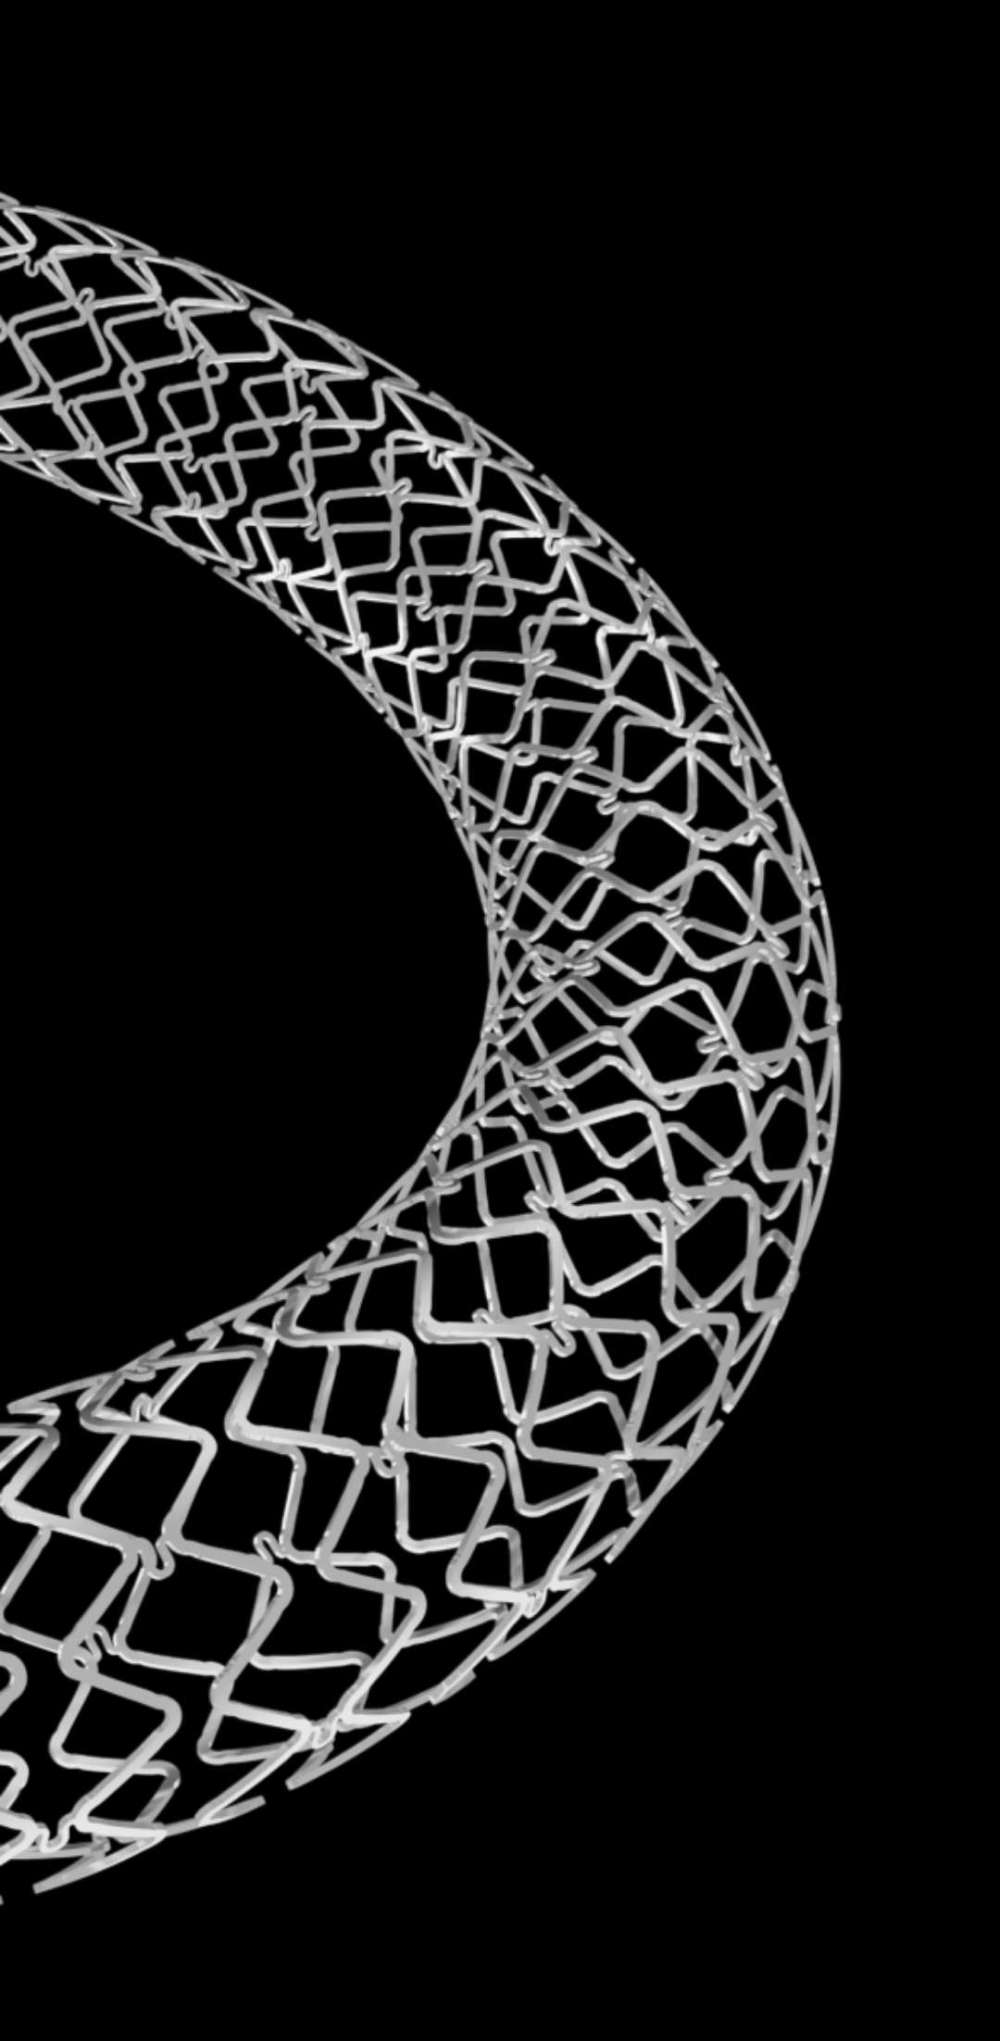

可吸收藥物洗脫支架盡管作為一種重要的研究熱點,但一直沒有很好解決可吸收材料問題。鐵基藥物洗脫可吸收外周支架采用的基材為滲入了0.05%氮的純鐵材料(Fe),所載藥物是西羅莫司。這款可吸收支架的優(yōu)勢包括:獨特的滲氮工藝使這款可吸收支架在維持足夠支撐力的同時支架壁厚可降低到60μm,支架規(guī)格豐富,最長可達118mm,專門為膝下動脈病變開發(fā);該支架通過聚乳酸(PLA)涂層載藥控制藥物釋放,能夠有效地抑制平滑肌細胞的增生和遷移;整個支架的降解周期為18-24個月。該支架是國際唯一的以鐵基為材料的全降解血管支架。